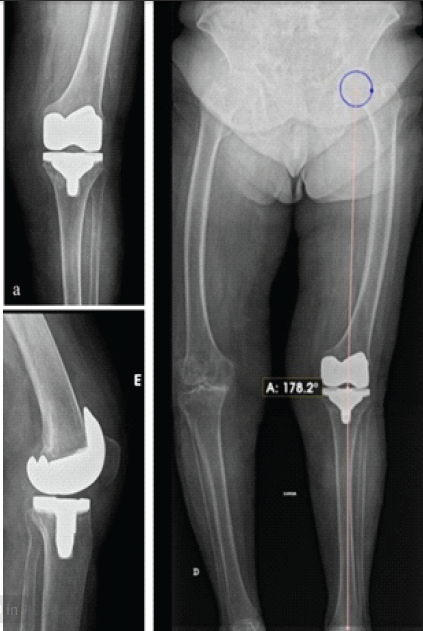

Tromboembolic prophylaxis was performed using subcutaneous enoxaparin for 28 days. On the 1st post-operative day, the patient began rehabilitation and full weight-bearing according to tolerance with two crutches. At 15 days postoperatively, the patient walked with two crutches, with extension to 0° and flexion to 100°. At 3 months, she ambulated with a single crutch, achieving full extension, 130° of flexion, and the surgical wound healed uneventfully. At 6 months of follow-up, she walked independently without crutches, maintaining a full range of motion and performing activities of daily living without limitations. Control radiographs confirmed satisfactory prosthetic alignment and restoration of the mechanical axis with 1.8° of valgus (Fig. 5a, b, c), a lateral distal femoral angle of 89.4°, and a medial proximal tibial angle of 90.7°.

Figure 5: (a) Six-month post-operative anteroposterior (AP) radiograph showing prosthesis in satisfactory coronal alignment. (b) Six-month post-operative lateral radiograph showing prosthesis in satisfactory sagittal position. (c) Six-month post-operative long-leg AP radiograph demonstrating restoration of mechanical axis to 1.8° of valgus.